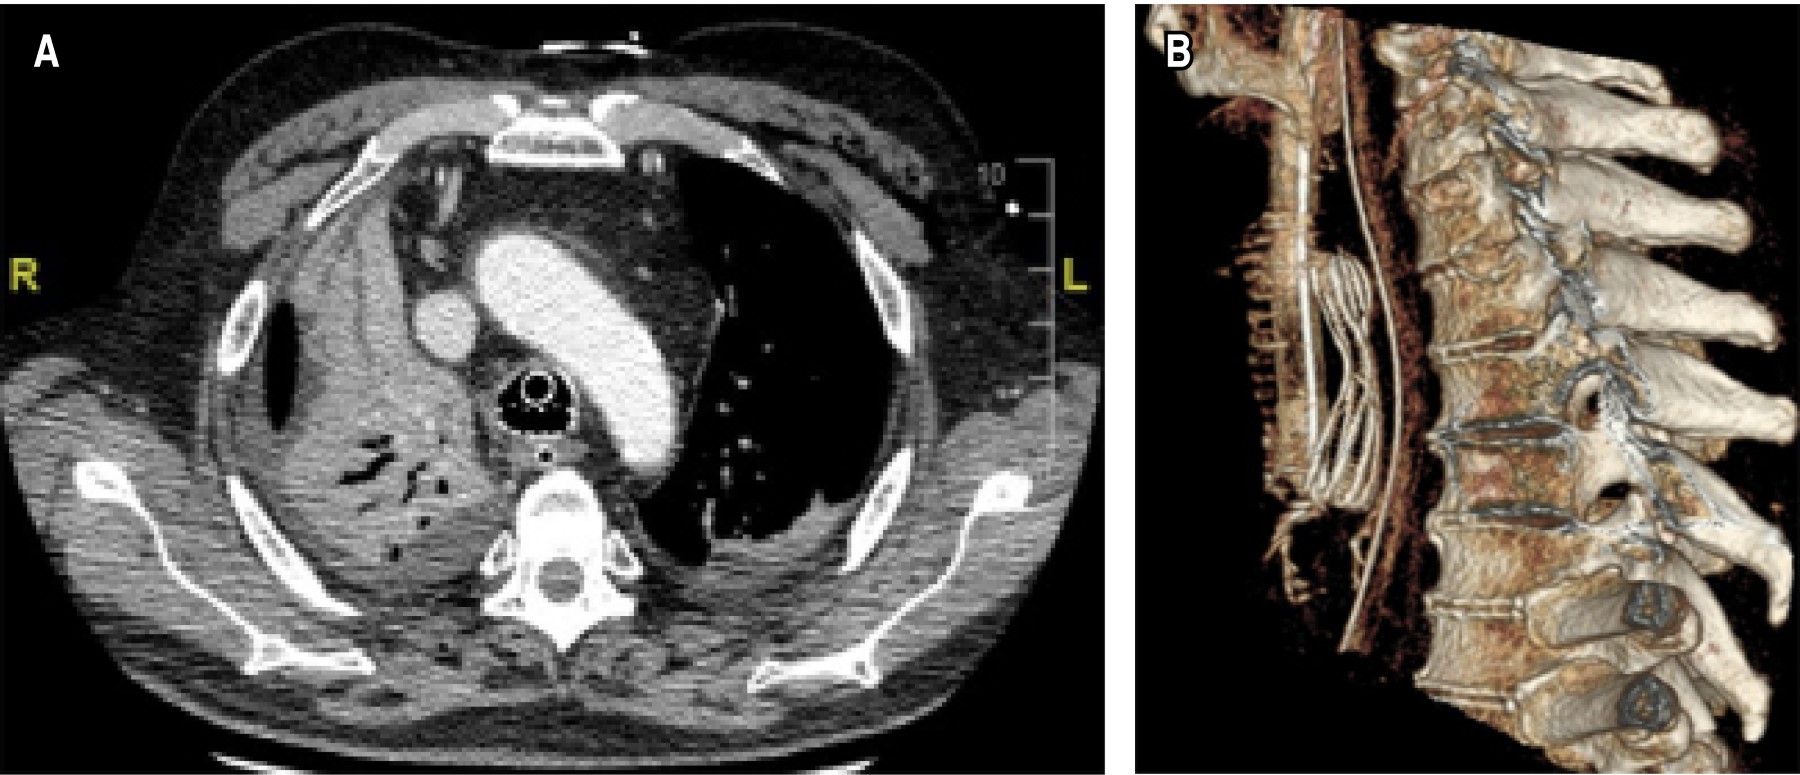

En nuestra experiencia, la intubación orotraqueal de estos pacientes, si no se realiza con las precauciones adecuadas, puede dar lugar a complicaciones como desplazamientos, falsas vías, neumotórax o roturas del stent. La presencia de un desplazamiento como el de la imagen (Figura 1) es una situación de extrema gravedad, tanto por la imposibilidad de ventilar al paciente de forma satisfactoria debido al sellado inadecuado de la vía aérea, como por la producción de un cuadro de neumotórax importante con posible amenaza para la vida. Además, el abordaje de la vía aérea de estos pacientes puede verse aún más dificultado si nos encontramos ante una situación emergente o con mala visualización glótica, donde la manipulación excesiva o a ciegas puede favorecer las lesiones traqueales y la migración del dispositivo, presentando también un obstáculo añadido para la realización de traqueostomías de emergencia. Las guías de vía aérea difícil suelen omitir a este subgrupo de pacientes entre los diferentes perfiles a tener en cuenta de cara a una posible intubación difícil, focalizándose más en aspectos que afectan a la vía aérea superior, y hacen que esta condición de la historia clínica del paciente pueda pasar desapercibida para el anestesiólogo, dando lugar, posteriormente, a una complicación fatal cuando se lleve a cabo una anestesia general.

Figura 1